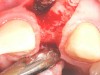

Fig 22. A straight healing abutment was attached to the implant. The barrier (held back with the periosteal elevator) was placed before the bone graft insertion.

Figure 22

Fig 23. The healing abutment in place. Horizontal and vertical incisions were sutured.

Figure 23